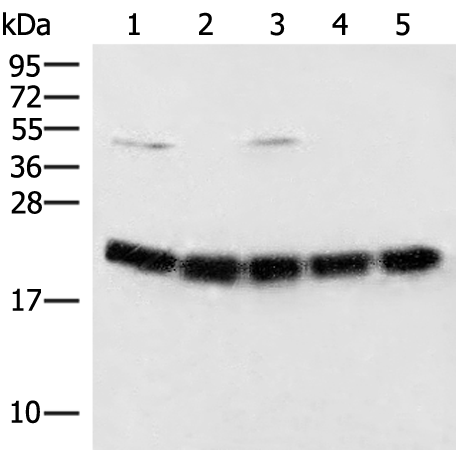

分类: 科研抗体货号: P05755别名: E2F-8应用: WB,IHC反应种属: Human, Rat